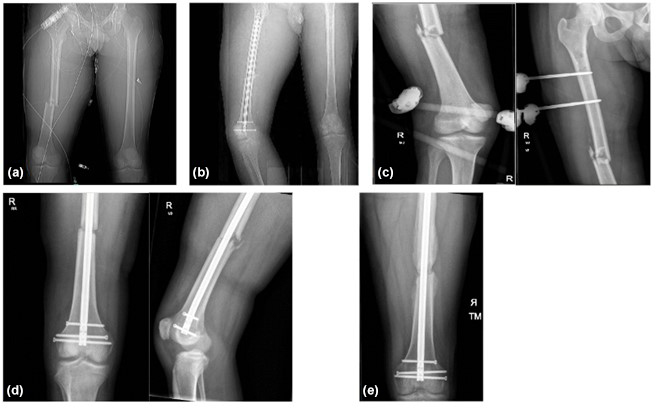

We report a case of post-traumatic Metamycoplasma hominis fracture-related infection of the right femur in a young male with no identified immunodeficiency. Treatment required multiple washouts and femoral nail revision, combined with 10 weeks of treatment with doxycycline and clindamycin.